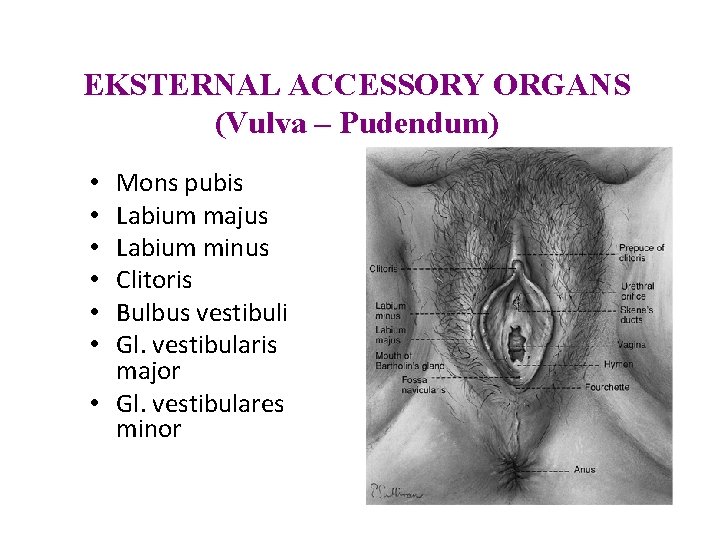

EKSTERNAL ACCESSORY ORGANS (Vulva – Pudendum) Mons pubis Labium majus Labium minus Clitoris Bulbus vestibuli Gl. vestibularis major • Gl. vestibulares minor • • •

Labium Majus Pudendi • • • Correspond to the scrotum Includes numerous hairs Rima pudendi Commisura labiorum ant. Commisura labiorum post. Lig. rotundum Rima pudendi Commissura post